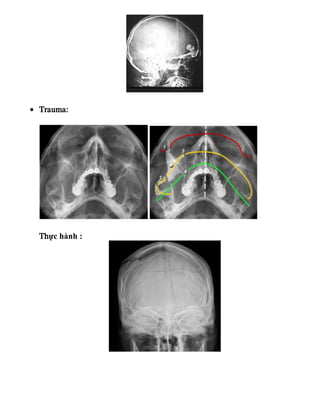

• Trauma:

Thực hành :